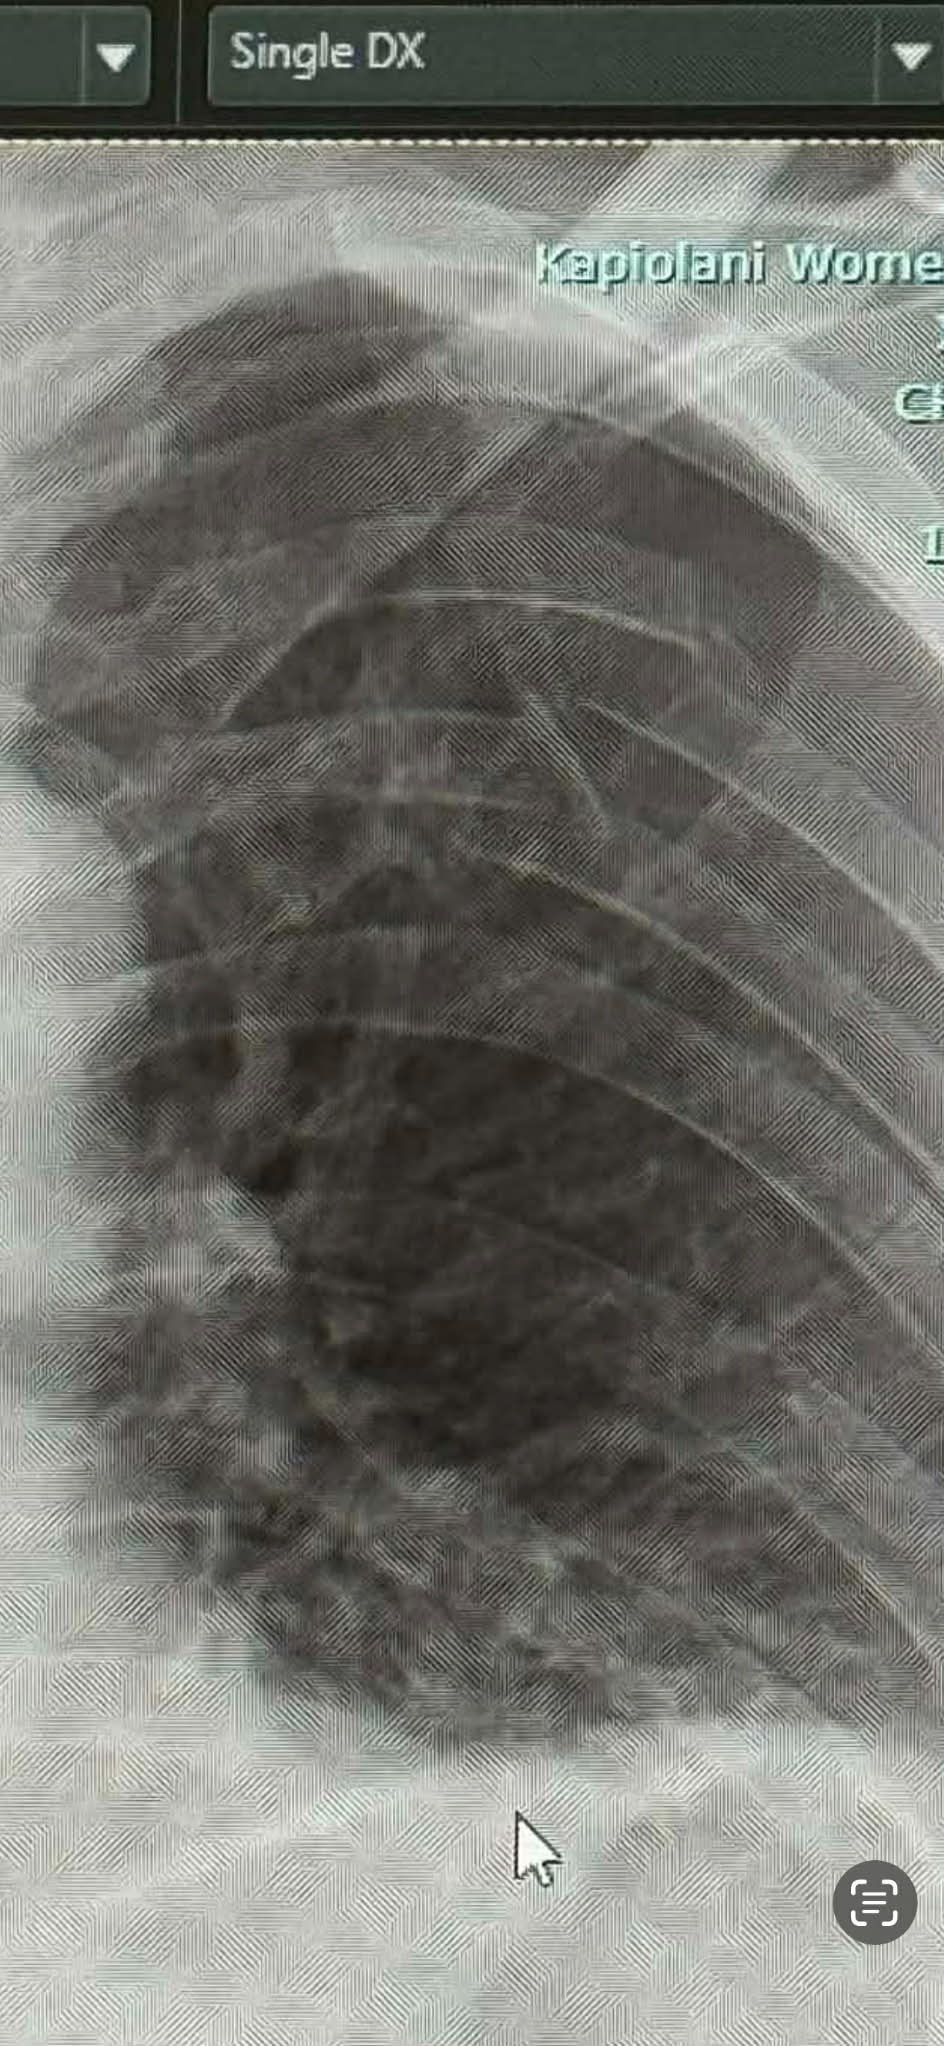

Recently, my son Ryan Peery was involved in a severe accident that has left him with serious injuries, including four broken ribs, a punctured lung, and extreme contusions to both of his legs. The accident has turned his life upside down, and the road to recovery will be long and challenging. Ryan is currently in recovery, but the extent of his injuries means he will be unable to work for several months as he undergoes treatment and physical therapy.